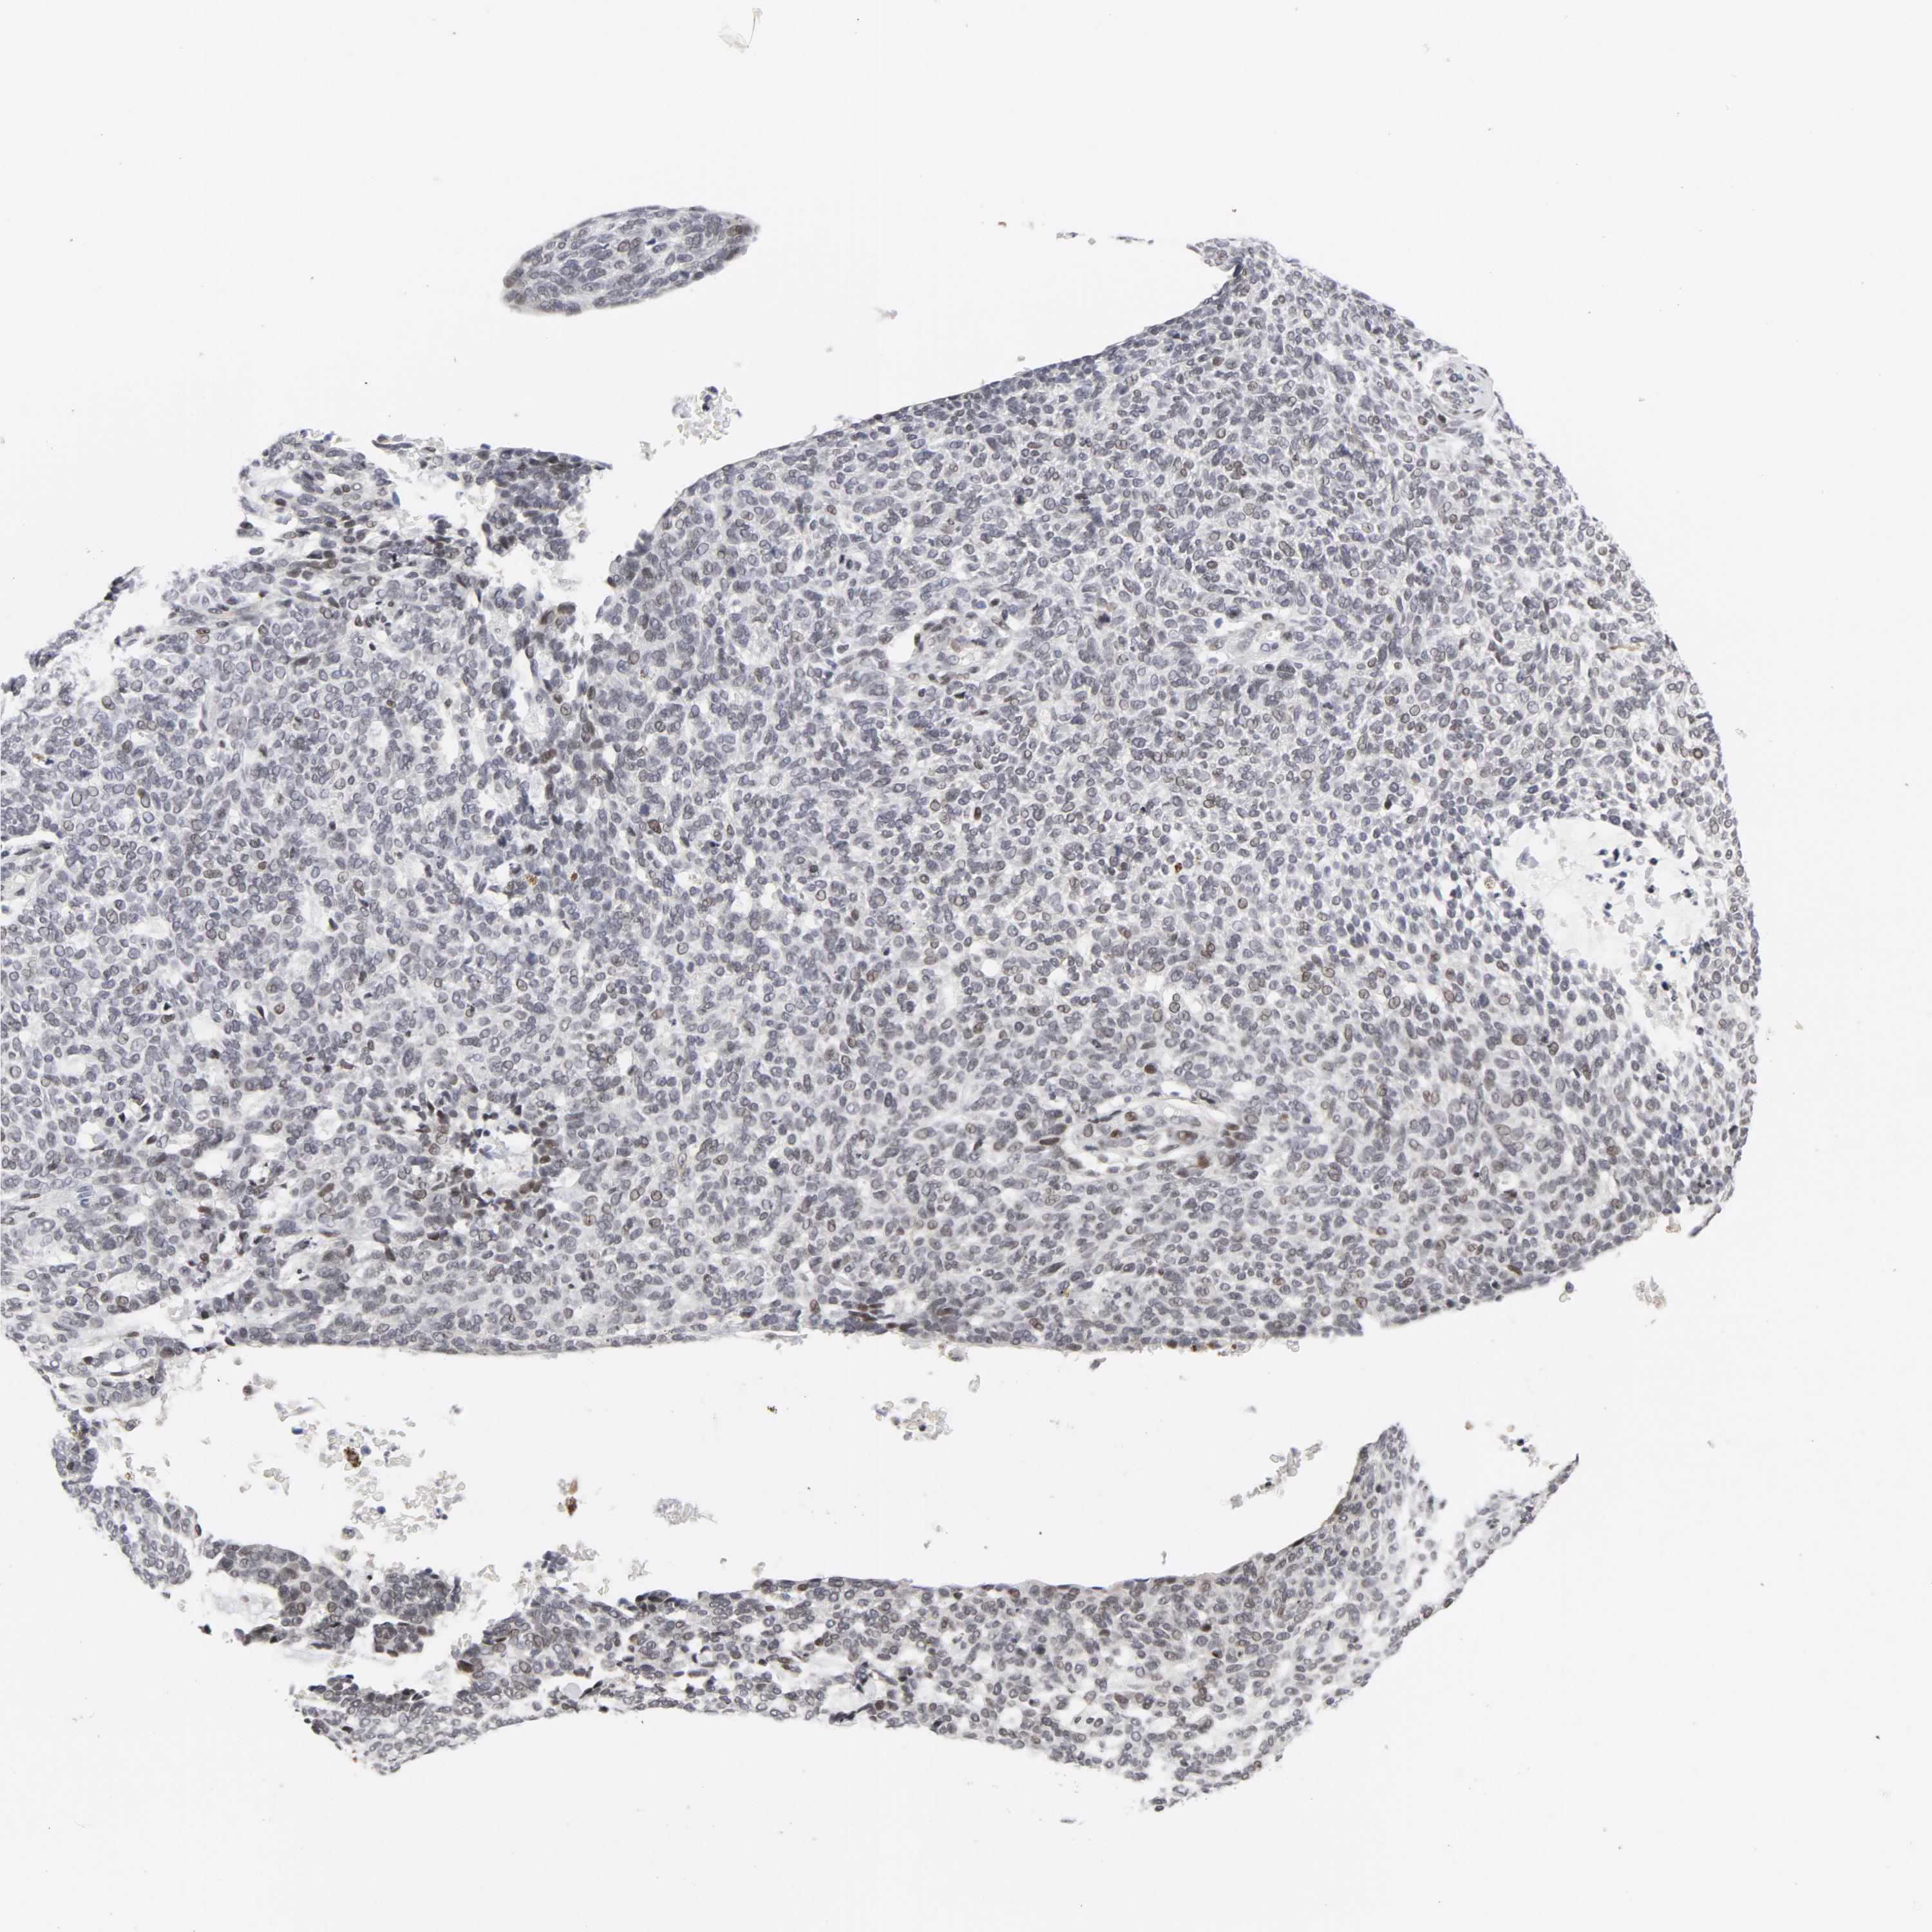

SKIN CANCER - Protein expressioni

A mouse-over function shows sample information and annotation data. Click on an image to view it in a full screen mode. Samples can be filtered based on level of antibody staining by selecting one or several of the following categories: high, medium, low and not detected. The assay and annotation is described here.

Antibody stainingi

Antibody staining in the annotated cell types in the current human tissue is reported as not detected, low, medium, or high, based on conventional immunohistochemistry profiling in selected tissues. This score is based on the combination of the staining intensity and fraction of stained cells.

Each image is clickable and will lead to virtual microscopy that enables deeper exploration of all samples and also displays staining intensity scores, fraction scores and subcellular localization as well as patient and tissue information for each sample.

Antibody HPA052625

Basal cell carcinoma

BCC, low aggressive